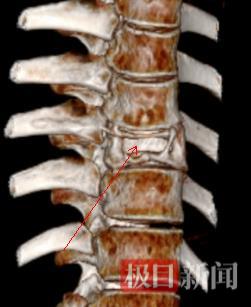

该院胸外科副主任刘小玉接诊后发现,患者不仅胸腔内形成感染性脓胸,他的胸椎也遭到病菌的侵蚀。三维成像清晰地显示,第九节胸椎骨约一半的骨质已经被蛀空,随时都可能发生骨折或因挤压脊髓而导致瘫痪。

三维成像画面中,胸椎骨病变清晰可见